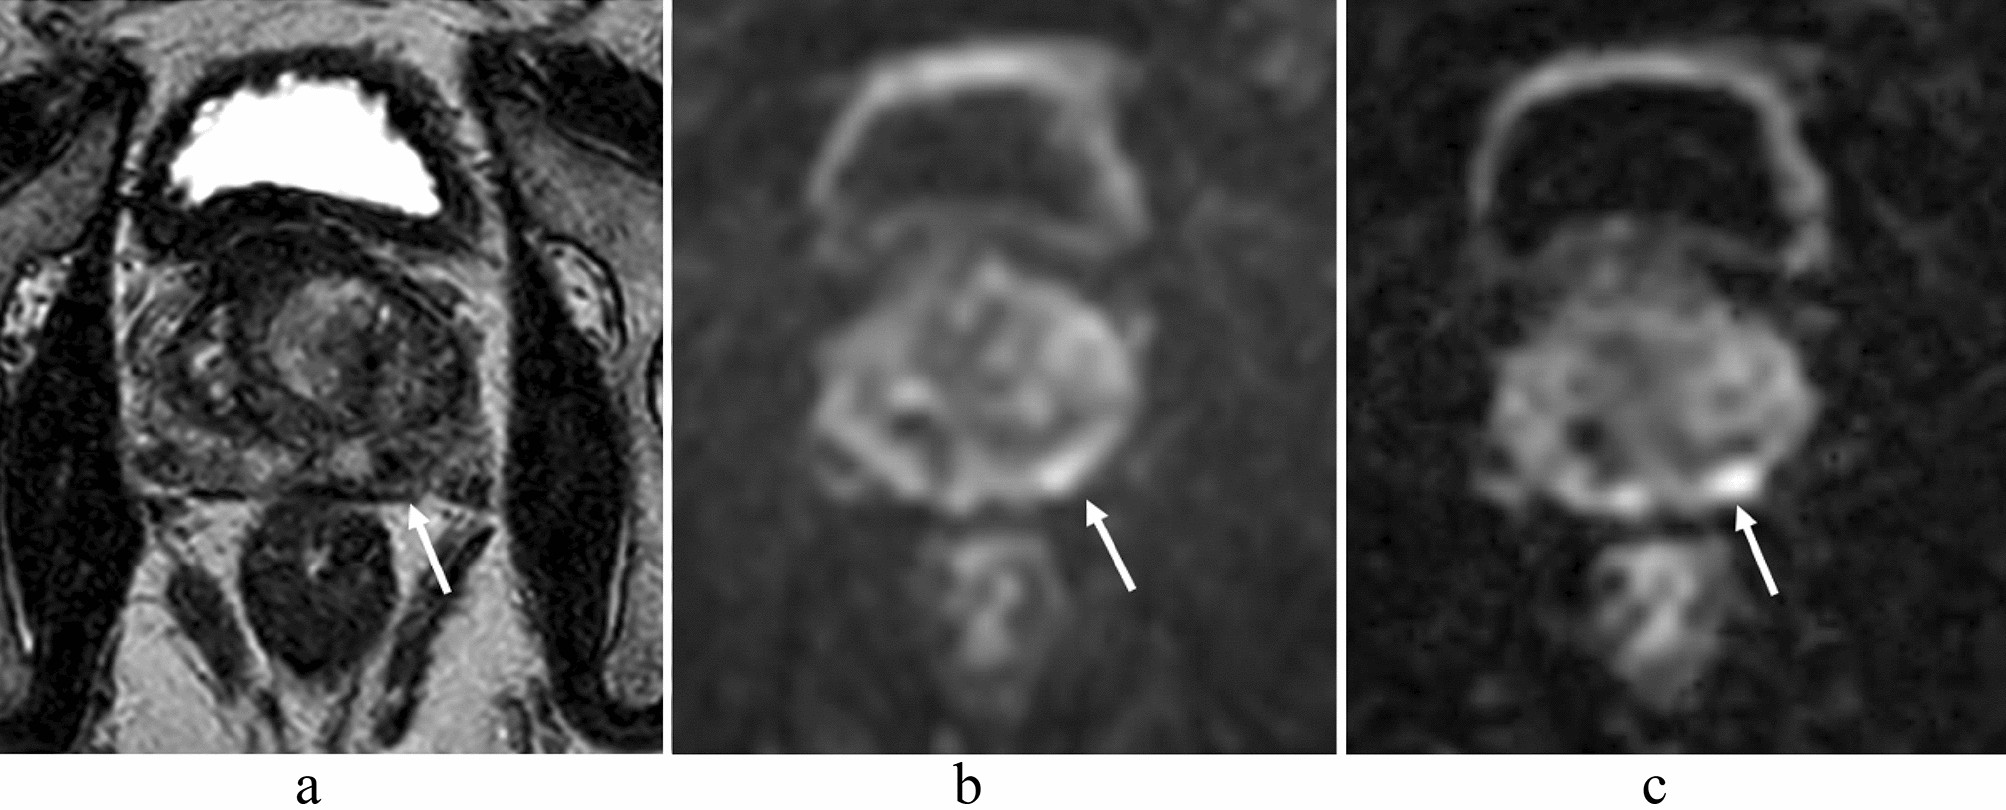

A 58-year-old man with prostate cancer (PSA level, 9.43 ng/mL; Gleason score, 4 + 3) in the left peripheral zone. A homogeneous hypointense lesion is seen on T2-weighted imaging (a) (arrow). A focal hyperintensity is depicted clearly on msEPI DWI (c) (arrow). Lesion conspicuity is lower in ssEPI DWI (b) than in msEPI DWI (c) (arrow). PSA prostate-specific antigen, msEPI multi-shot echo-planar imaging, DWI diffusion-weighted imaging, ssEPI single-shot echo-planar imaging.